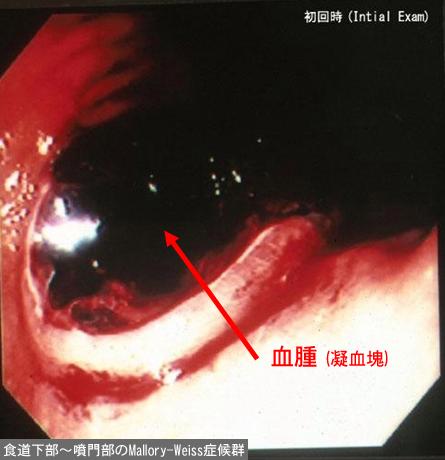

症例提示(所在地,施設名等): 東京都・ 国立がんセンター中央病院と九州がんセンターの共同作成

画像ID:11958

疾患(病理主体)の分類その他/

部位(臓器別)食道/下

検査方法内視鏡